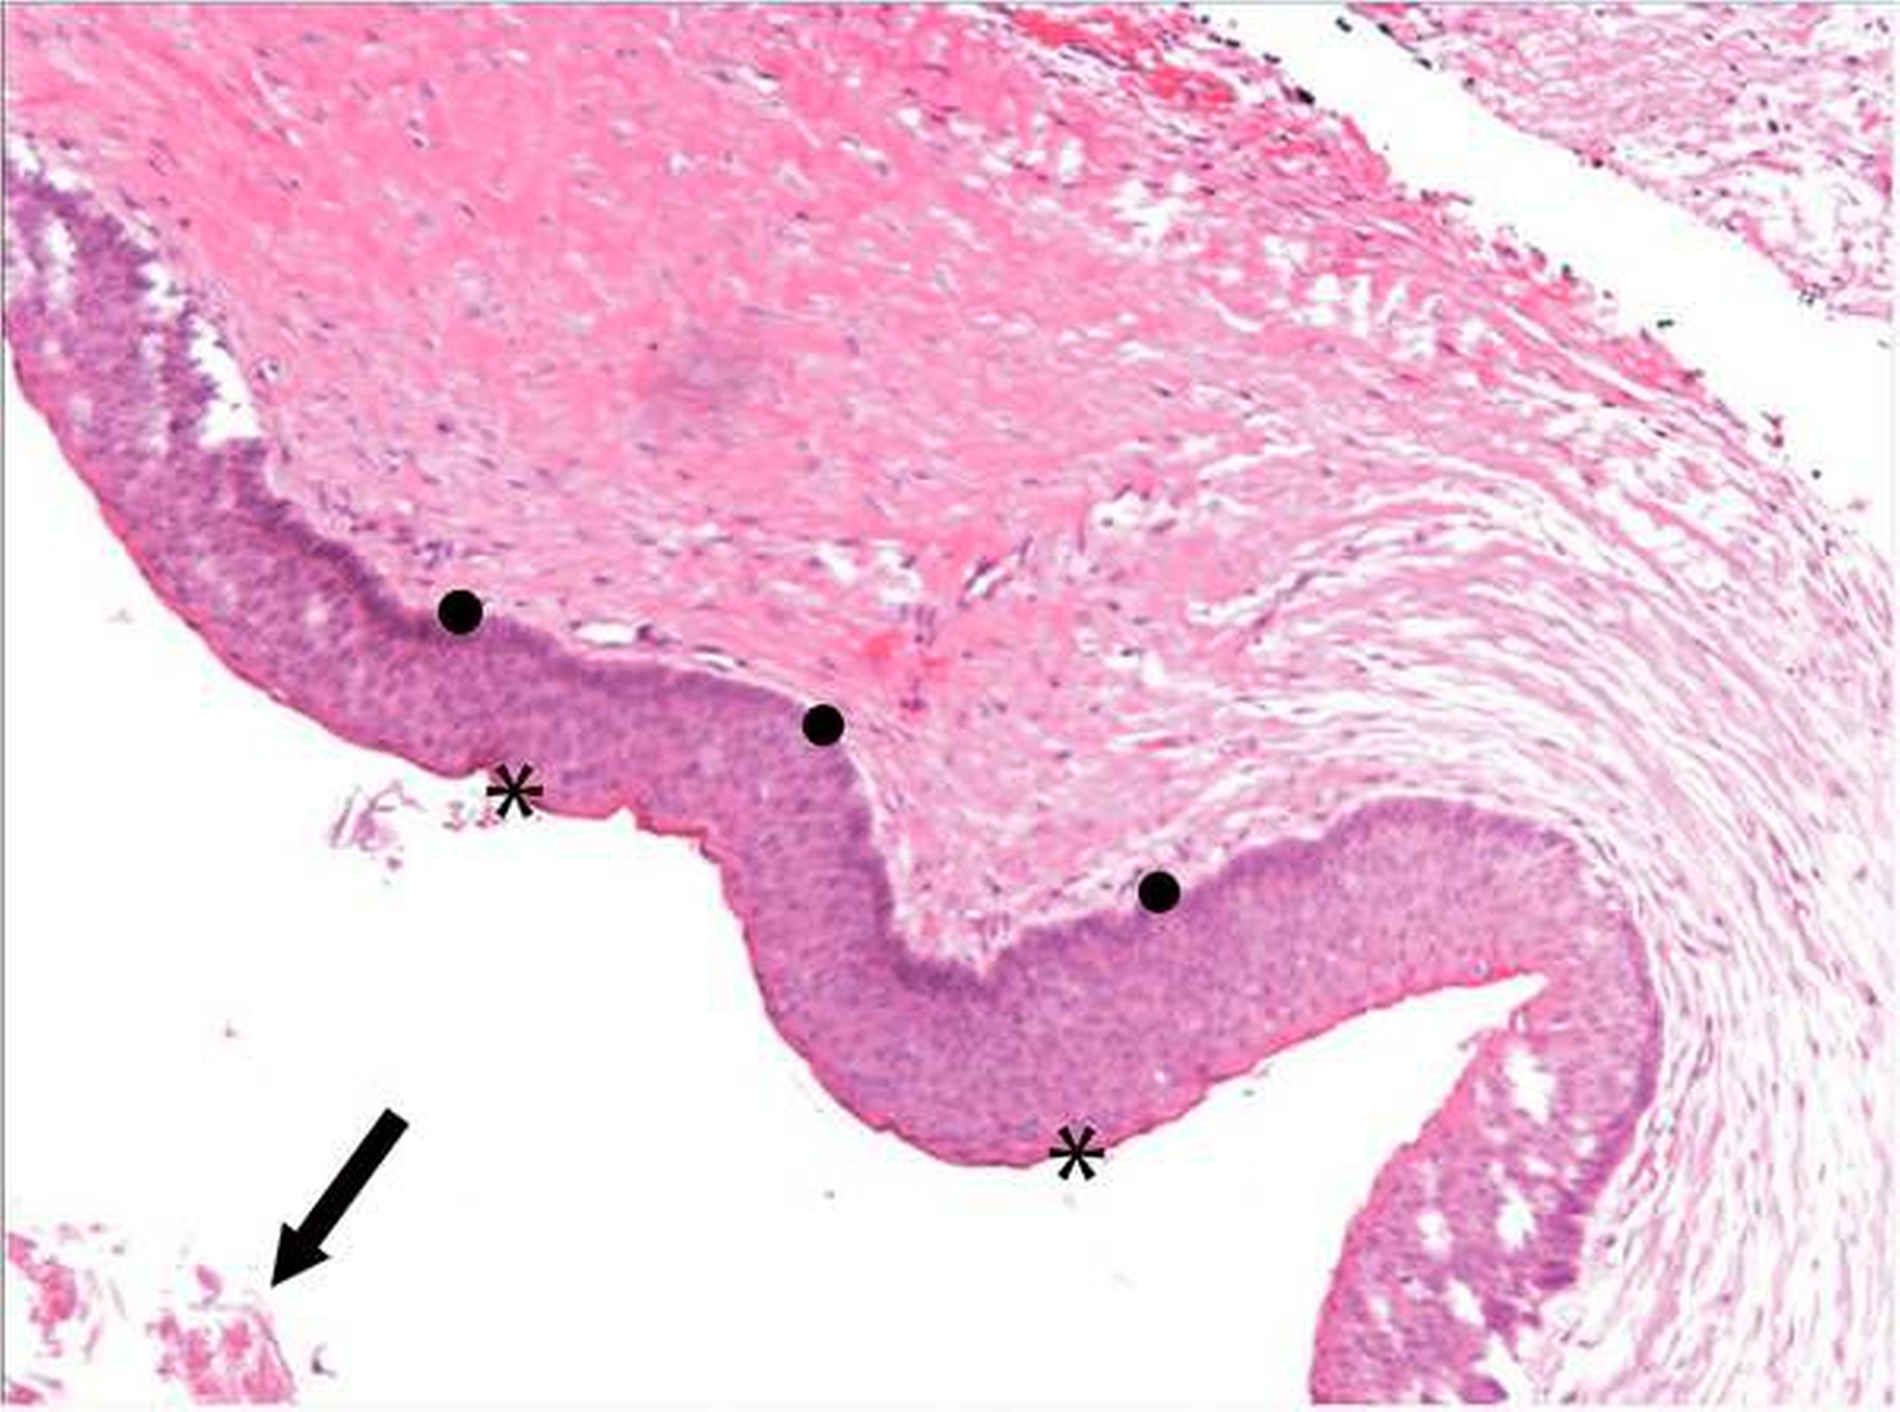

Zur Diagnosesicherung erfolgte eine Probeentnahme aus den zystischen Läsionen. Die pathohistologische Untersuchung ergab die Diagnose zweier odontogener Keratozysten (Abbildungen 7 und 8). Mit dem Ziel des Erhalts der Zähne 34–44 erfolgten die Enukleation der Keratozysten mit peripherer Ostektomie unter Schonung der Zahnwurzeln und die Defektfüllung mit autologer Beckenkammspongiosa und Knochenersatzmaterial (Bio-Oss®, Geistlich) über einen intraoralen Zugangin Allgemeinanästhesie. Im Rahmen desEingriffs wurde der retinierte und verlagerte Zahn 33 operativ entfernt. Abbildung 6 zeigt die postoperative Orthopantomografie mit Beckenkammspongiosa in den Defekten.

Histologisch werden zwei Varianten unterschieden: die ortho- und die parakeratinisierte Form, wobei die parakeratinisierte Keratozyste mit über 80 Prozent deutlich häufiger auftritt. Makroskopisch enthält die glattwandige Zyste mit dünnem, fragilem Balg ein chromgelbes Sekret, das in Konsistenz und Farbe Vanillepudding ähnelt.

Mikroskopisch imponiert der Zystenbalg typischerweise mit mehrschichtigem Plattenepithel, in der Regel etwa zehn Zellschichten sowie einer basalen Kernpalisade und einer scharfen, gewellt verlaufendenluminalen Begrenzung durch eine zarte Parakeratosezone, das heißt, eine Verhornungszone mit residuellen Kernen der verhornten Keratinozyten, von der sich zellkernlose Hornschuppen lösen, die sichdann im Zystenlumen finden. Randständige Tochterzysten sind gelegentlich nachweisbar und können die hohe Rezidivrate erklären. Sekundäre Infektionen können das histologische Erscheinungsbild verändern und zu einem Verlust der typischen histologischen Merkmale führen, was die sichere Zuordnung der Befunde erschwert [Bakos etal., 2014]. Maligne Transformationen zueinem Plattenepithelkarzinom wurden beschrieben, gelten allerdings als Rarität [Gardner, 1975].